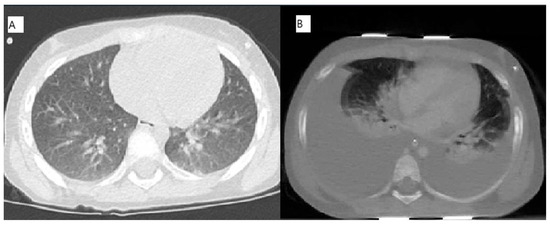

2.1. Case 1 [Unique Patient Number (UPN) 1069066]

2.2. Case 2 (UPN 1077926)

2.3. Cases 3 (UPN 1076952) and 4 (UPN 1077940)